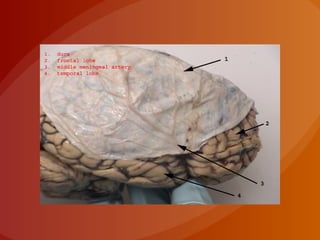

MENINGES